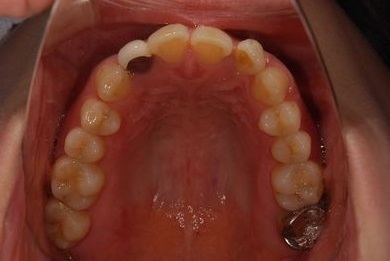

治療前

• 治療前